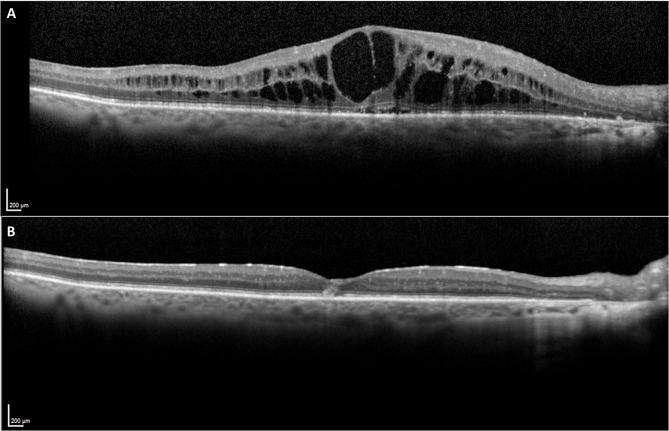

Eight eyes from 8 patients were included in the study. Median (95% Confidence-interval) BCVA was significantly improved from 60.0 (50.05-69.95) letters at baseline to 80.15 (77.25-85.00) letters at month-36, p = 0.043. At the last follow-up visit, 5 (62.5%) eyes gained ≥ 15 letters, without any eye experiencing a loss of BCVA compared to baseline. There was significant CRT reduction from baseline (median: 497.5 μm; 95%CI: 380.0-596.0 μm) to month-36 (Median: 252.0 μm; 95%CI: 242.0-268.0 μm); p = 0.012. Regarding safety, IOP remained stable from baseline (median: 14.5mmHg; 95%Confidence-interval: 12.0-23.0 mmHg) to the last follow-up visit (median: 13.5mmHg; 95% Confidence-interval: 9.0-19.0 mm Hg); p = 0.123.

8例患者的8只眼纳入研究。BCVA中位数(95%置信区间)从基线时的60.0(50.05 - 69.95)行显著提高至36个月时的80.15(77.25 - 85.00)行,p = 0.043。在最后一次随访时,5只眼(62.5%)视力提高≥15行,与基线相比无眼出现BCVA下降。从基线(中位数:497.5μm;95%CI:380.0 - 596.0μm)到36个月时(中位数:252.0μm;95%CI:242.0 - 268.0μm)CRT显著降低;p = 0.012。关于安全性,眼压从基线(中位数:14.5mmHg;95%置信区间:12.0 - 23.0mmHg)到最后一次随访时保持稳定(中位数:13.5mmHg;95%置信区间:9.0 - 19.0mmHg);p = 0.123。